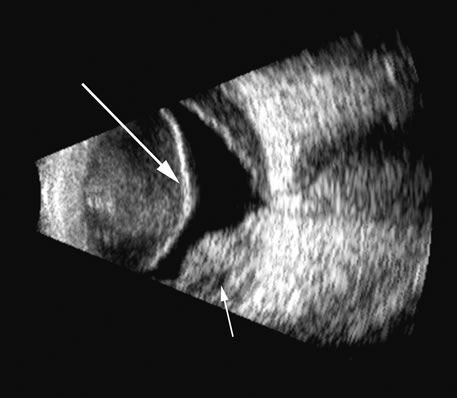

Fig. 4. A clinically well-placed posterior chamber intraocular lens nevertheless had patient complaints of photophobia and irritation due to a folded haptic (arrow).

Fig. 5. An anterior chamber intraocular lens has had the support haptics dislocate posterior to the iris plane and can be seen as typical foreign body echogenic reflections (arrows).